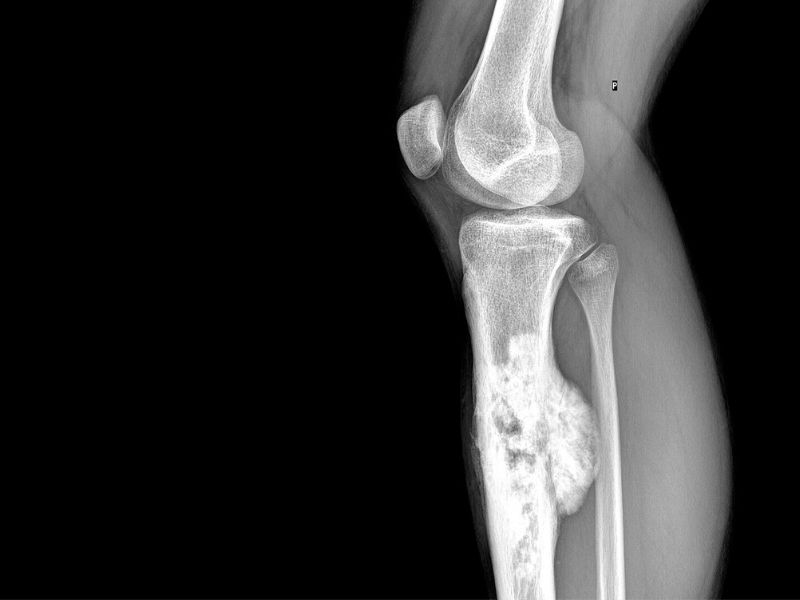

U xương sụn thường phát triển chậm, gây đau hoặc biến dạng nhẹ ở khu vực xương bị ảnh hưởng. Khi khối u lớn, bệnh nhân có thể cảm thấy khó chịu hoặc bị hạn chế vận động. Trên ảnh chụp X-quang, u xương sụn cho thấy hình ảnh nấm sụn có cuống, phát triển gần hành xương.

- Chụp X-quang: Là phương pháp chẩn đoán hình ảnh đầu tiên và phổ biến nhất để phát hiện bất thường trong cấu trúc xương, giúp xác định vị trí khối u, hình dạng, mật độ và mức độ ảnh hưởng đến mô xương xung quanh. Hình ảnh X-quang có thể cho thấy các dấu hiệu như vùng mất xương (tiêu xương) hoặc tạo xương bất thường.